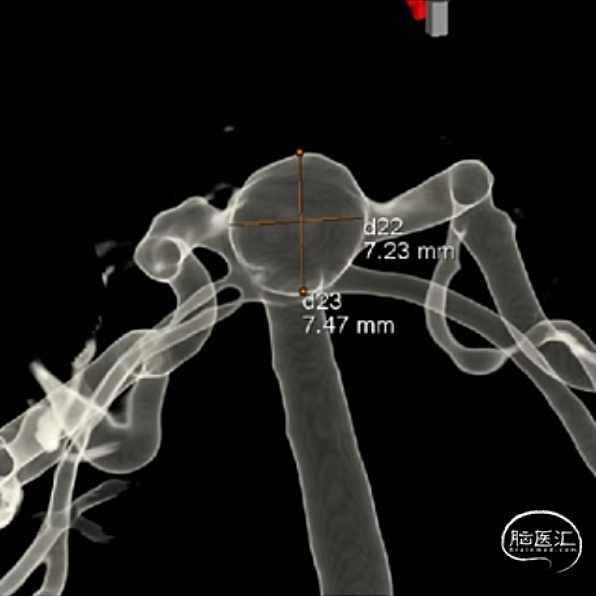

判断:基底动脉尖部动脉瘤WEB™术。

经测量可得动脉瘤宽度平均值为7.28mm,动脉瘤最小高度为4.91mm,参考尺寸选择表,选择WEB™ SL 8*4。

绝对瘤颈宽,右侧P1与瘤颈部分融合,容易疝出从而遮挡P1,应提前进行“分支保护”。

经VIA™微导管推送并释放WEB™ SL 8*4。

6个月后随访,Boss评分0级,动脉瘤完全闭塞不显影,WEB™完全栓塞。